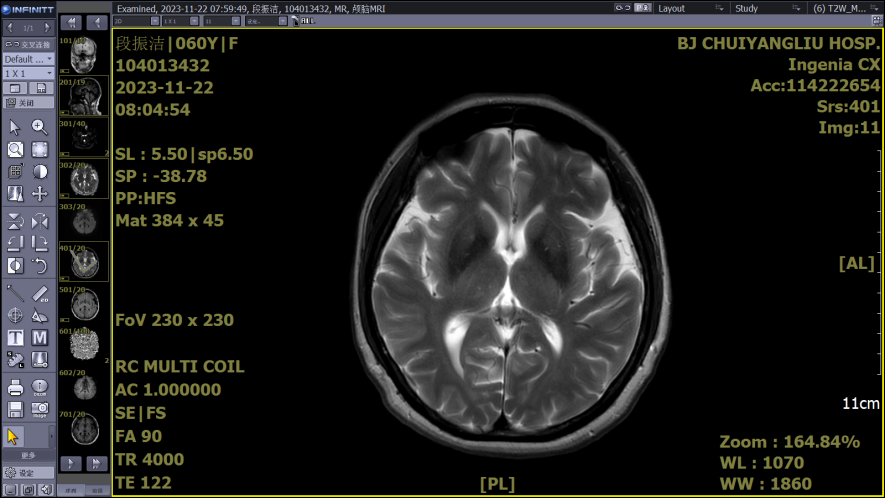

二、磁共振成像(MRI)

MRI是一种断层成像技术,它利用磁共振现象从人体中获得电磁信号,并重建出人体信息,对软组织分辨能力高于CT数倍,可比CT更有效和早期地发现病变,对颅脑、脊柱和脊髓等解剖和病灶的显示优于CT。磁共振血管成像借其“流空效应”,可不用血管造影剂显示血管结构。缺点是核磁共振检查室内存在非常强大的磁场,因此体内留有某些金属、安装心脏起搏器者不宜;因检查所需时间较长,对病情危重、幽闭恐惧的患者不宜。由于钛金属不受磁场的吸引,因此体内有钛金属内固定物的患者可以进行核磁共振检查。